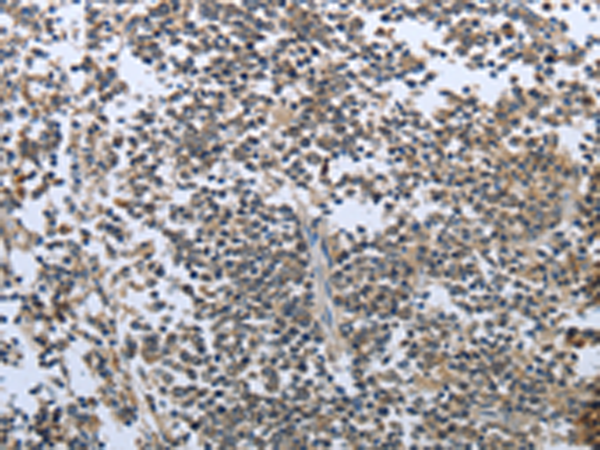

分类: 科研抗体货号: P00757别名: CART1; MLN62; RNF83应用: WB,IHC反应种属: Human, Mouse